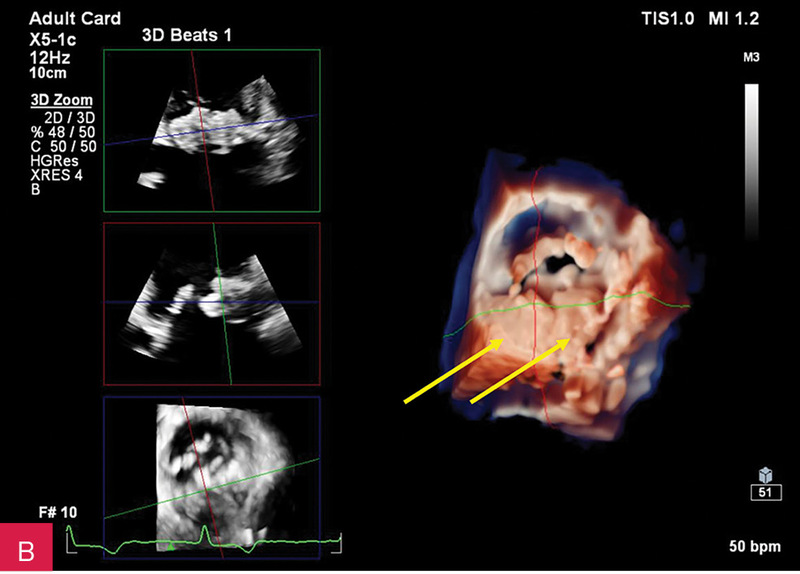

Rycina 4A, B. Badanie echokardiograficzne przezklatkowe trójwymiarowe (3D TTE) – widok od strony lewej komory zastawki mitralnej i guzowatej zmiany o nierównej powierzchni (A) wraz z prezentacją zmiany w przekrojach wykonanych na podstawie 3D TTE (B)